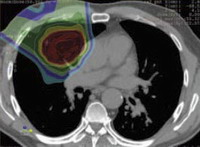

На протонную терапию онкологи возлагают большие надежды, так как она имеет значительные преимущества перед традиционными методами радиационной терапии. Целевое облучение пучком протонов значительно снижает уровень облучения здоровых тканей и дает возможность повысить дозу облучения опухолевых клеток. При неметастазированных опухолей – эффективность лечения возрастает более чем на 50 %.

Центр Протонной терапии в Мюнхене является первым центром в Европе, задуманным и созданным исключитель но для лечения пациентов, а не открытым на базе научно-исследовательского центра. Оснащение Центра даёт возможность облучать опухоли, расположенные на глубине до 38 см. Благодаря отсутствию облучения тканей за опухолью стало возможным использовать высокие дозы излучения для таких форм рака, лечение которых до сих пор было слишком опасным из-за соседства с чувствительными органами (такими, как спинной мозг, мозговой ствол, печень и лёгкие). Обычным явлением стало облучение глазных опухолей без повреждения при этом зрительного нерва, роговицы и тканей мозга. Для лечения детей, по мнению международных специалистов, должна использоваться протонная терапия. Подробнее